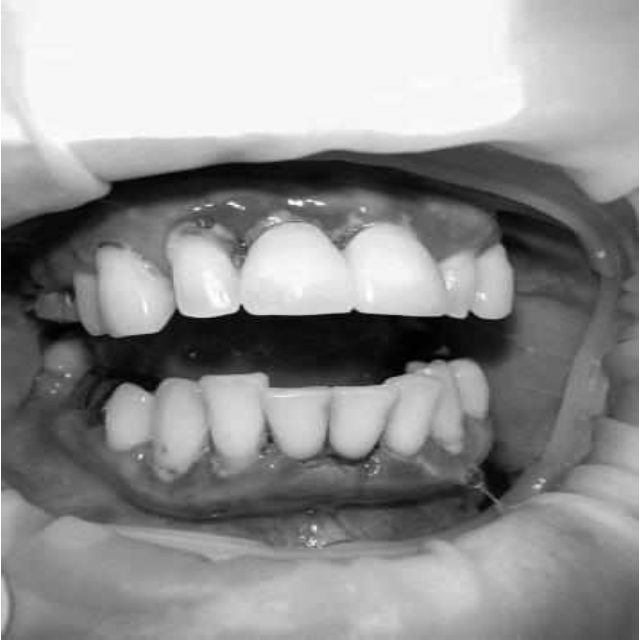

За пародонтологическим лечением обратилась женщина 61 года с жалобами на неприятный запах из полости рта, кровоточивость десен при чистке зубов, подвижность зубов, несостоятельность ортопедических конструкций.

Ранее у пародонтолога не наблюдалась. При осмотре выявлены: неудовлетворительная индивидуальная гигиена полости рта, пародонтальные карманы до 7 мм, обильная кровоточивость и гноетечение из пародонтальных карманов, подвижность зубов 4.2, 4.1, 3.1, 3.2 II степени, обильные над- и поддесневые зубные отложения (рис. 1). На ортопантомограме отмечается резорбция костной ткани до ½ длины корня, очаги остеопороза (рис. 2). Пациенту был поставлен диагноз хронический генерализованный пародонтит тяжелой степени тяжести. При осмотре была составлена пародонтограмма с использованием компьютерного зондирования (рис. 3).

Рис. 1. Внешний вид

Через 6 месяцев при осмотре выявлен удовлетворительный уровень индивидуальной гигиены, отсутствие участков кровоточивости и гноетечения (рис. 4), пародонтальные карманы уменьшились в размерах (рис. 5). Пациент отмечает значительные улучшения. После стабилизации пародонтологического статуса пациент направлен для дальнейшего ортопедического лечения.

Рис. 4. Динамика результата через 6 месяцев